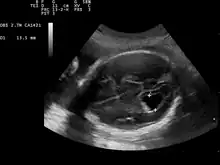

| Prenatal ultrasound showing a well defined hypoechoic lesion corresponding to a choroid plexus cyst | |

Choroid plexus cysts (CPCs) are cysts that occur within choroid plexus of the brain. They are the most common type of intraventricular cyst,[1] occurring in 1% of all pregnancies.[2]

CPCs can form within this structure and come from fluid trapped within this spongy layer of cells, much like a soap bubble or a blister. CPCs are often called "soft signs" or fetal ultrasound "markers" because some studies have found a weak association between CPCs and fetal chromosome abnormalities.